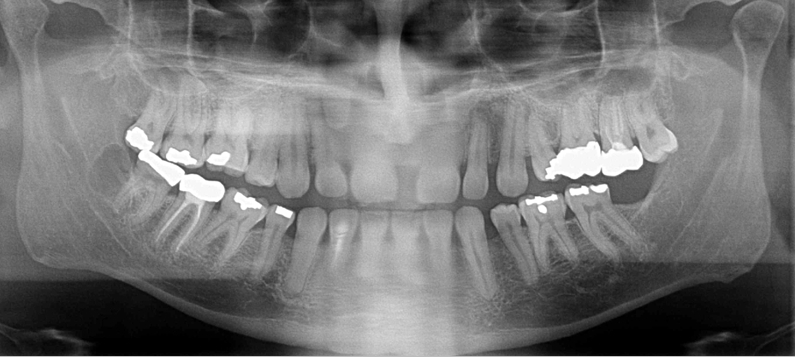

What is wrong with this image?

A

removable prosthodontic device